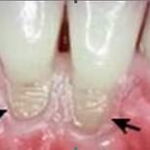

• Hôi miệng cũng có thể có nguyên nhân từ các bệnh về răng miệng. Nếu bạn không đánh răng mỗi ngày, những thức ăn dính trong miệng sẽ hấp thu vi trùng gây ra mùi hôi. Một lớp vi trùng sẽ đóng màng chân răng, nếu không được vệ sinh sẽ gây sưng chân nướu và sâu răng, tạo ra chứng hôi miệng. Những bộ răng giả đeo không vừa cũng có thể tạo ra những túi vi trùng gây ra chứng hôi miệng.